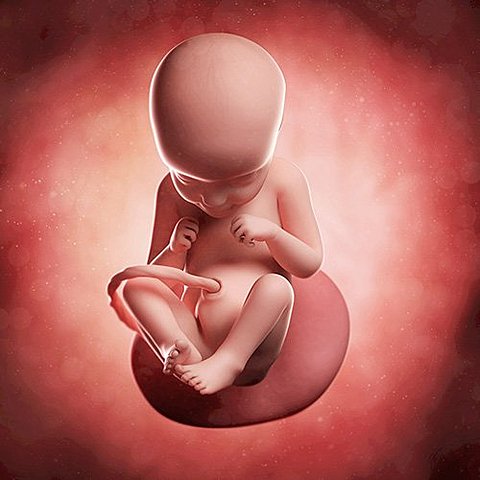

• semana 30 a 38

semana 30 a 38

El bebe ya se encuentra en la posición adecuada para el momento del parto. Su cráneo todavía no está totalmente sólido, ya que necesita pasar por el canal de parto. Al final de este período, el bebé puede alcanzar una talla de hasta 50 cm y un peso promedio de 3 kg. Hacia al final de la semana 38, el bebé está en condiciones de nacer.

• semana 39 a 40

semana 39 a 40

Durante las ultimas dos semanas se dedica a fortalecerse y ganar peso. Queda menos líquido amniótico en el útero. El vello lanugo casi ha desaparecido. El cerebro está perfectamente constituido. Puede diferenciar lo amargo de lo dulce y activar el sentido del olfato. Su corazón palpita a una velocidad de 120-160 pulsaciones por minuto. El bebé está listo para su nacimiento.